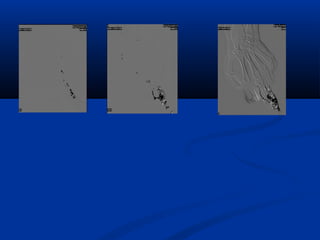

AVM of the hand. Slow venous filling. Direct stick with Foam.

Marked reduction in nidus filling.

Resolution of symptoms